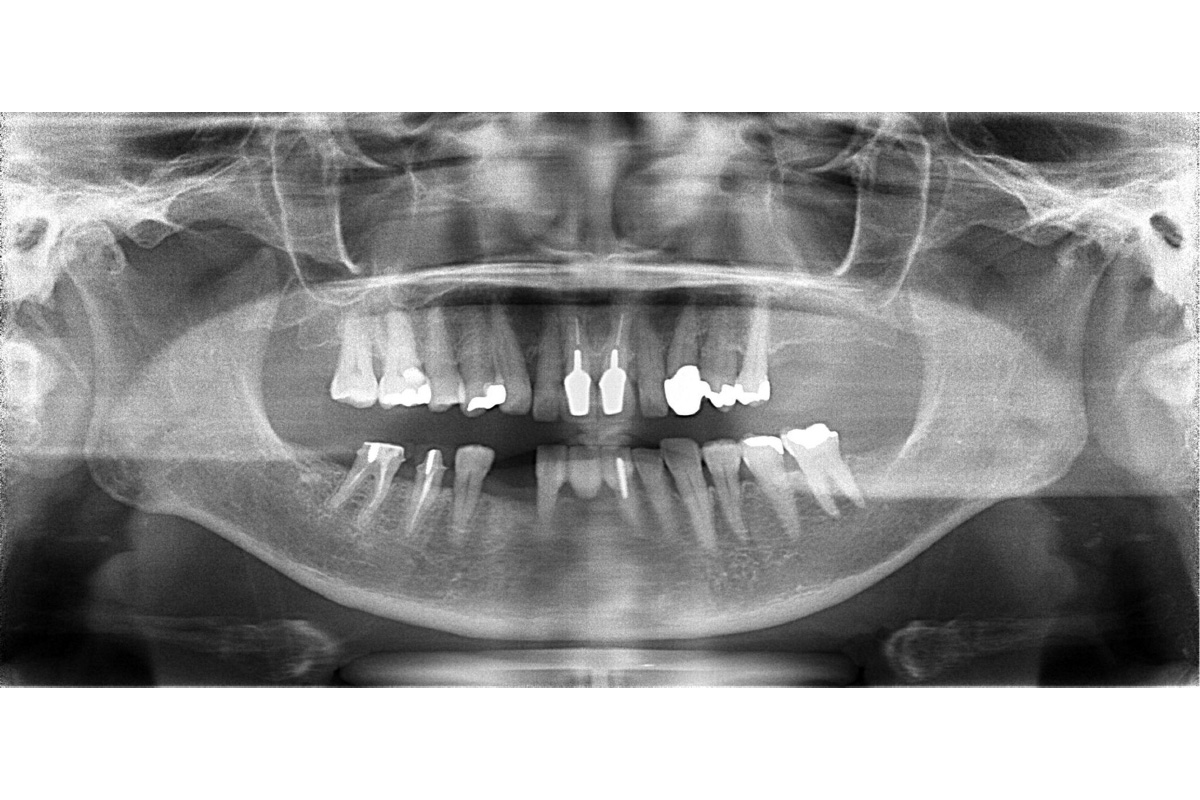

治療後

| 主訴 | 左下の歯を入れ歯以外で治したい。前歯のブリッジはそのままで治したい。 |

| 期間 | 5ヵ月 |

| 費用 | 566,500円(治療時) |

| 治療内容 | 骨造成 結合組織移植術 インプラント治療 |